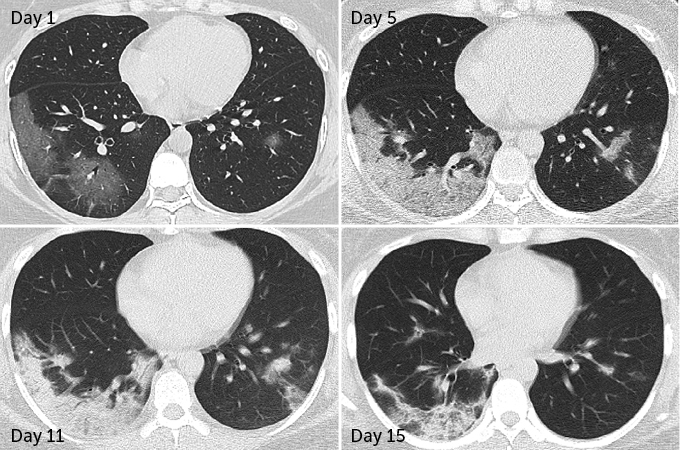

In 70 patients who survived COVID-19 pneumonia, 66 had some level of lung damage visible in CT scans taken before hospital discharge, researchers report March 19 in Radiology. The damage ranged from dense clumps of hardened tissue blocking blood vessels within the tiny air sacs called alveoli, which absorb oxygen, to tissue lesions around the alveoli, Yuhui Wang, a radiologist at Huazhong University of Science and Technology in Wuhan, China, and colleagues found.

But while initial lung images indicate that SARS and MERS typically set into just one lung, COVID-19 appears to be more likely to afflict both lungs right away. In 75 of the 90 patients admitted to Huazhong University Hospital with COVID-19 pneumonia from January 16 to February 17, damage was seen across both lungs, Wang and colleagues report. CT scans taken before hospital discharge revealed that 42 out of 70 patients displayed the type of lesions around the alveoli that are more likely to develop into scars.